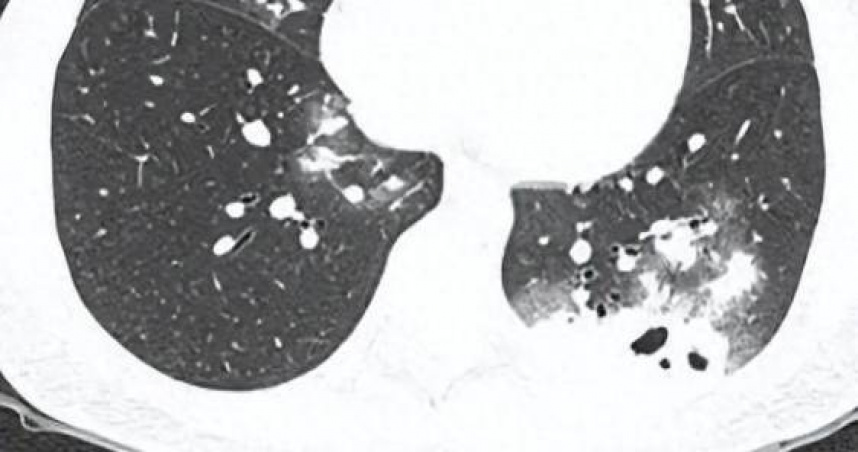

30歲女乾咳1週,肺部CT驚見「鬼臉」。(圖/翻攝自广东广播电视台 微博)

大陸1名30歲的夏姓女子(化名)近日因持續乾咳,到廣醫附屬番禺中心醫院呼吸科門診就診,胸部CT(胸部電腦斷層掃描)顯示雙肺多發感染伴多發空洞形成,收入呼吸與危重醫學科一區住院治療。該科主任醫師劉知陶查房時,敏銳捕捉到CT上形似「鬼臉」的特殊影像(即鬼臉症),高度懷疑感染隱球菌肺炎。